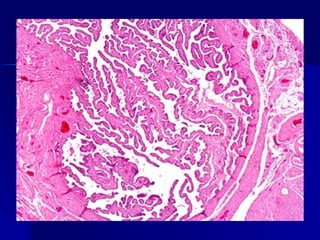

Células de la inflamación aguda a) Leucocitos polimorfonucleares rodeando un gránulo actinomicósico.  b) Células mononucleares: linfocitos, monolitos y células plasmáticas.

Células de lainflamación aguda a) Leucocitos polimorfonucleares rodeando un gránulo actinomicósico. b) Células mononucleares: linfocitos, monolitos y células plasmáticas.